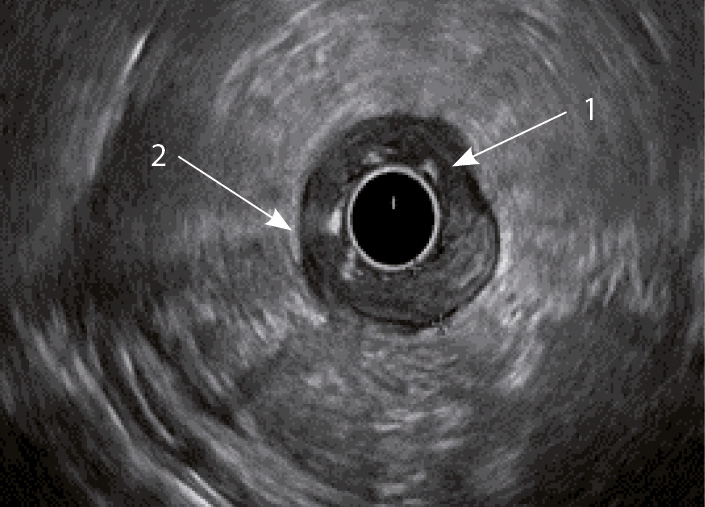

При ВЗК в стадии обострения стенка кишки утолщается, при этом в зависимости от нозологии увеличение размера кишки происходит за счет разных слоев кишечной стенки (рис. 1–4).

Рис. 4. Эндосонографическая картина толстой кишки при болезни Крона; 1 – отсутствие дифференцировки слоев кишечной стенки; 2 – утолщение стенки толстой кишки за счет всех слоев

Толщина стенки толстой кишки при ЯК была в диапазоне от 2,7 до 5,5 мм (3,96 ± 0,13), при БК – от 3 до 11 мм (5,66 ± 0,36), в контрольной группе данный показатель не превышал 3,1 мм, а минимальная толщина была 1,6 мм (2,62 ± 0,11). Анализ толщины стенки в разных группах выявил статистически значимую разницу величины показателей между больными с ВЗК и группой контроля (р = 0,002), между ЯК и БК (р = 0,002). При этом при сравнении БК и группы контроля коэффициент достоверности оказался выше, чем при ЯК (р < 0,001 и р = 0,002 соответственно) (см. рис. 1).

Кишечная стенка статистически значимо чаще утолщалась за счет слизисто-подслизистого слоя при ЯК, чем при БК: в 82 и 7,14% соответственно; диагностическая чувствительность данного признака была 82%, а специфичность – 93% (табл. 1). При БК изменение стенки толстой кишки за счет трансмурального утолщения выявлялось статистически значимо чаще (68%), чем при ЯК (9%) (чувствительность 68%, специфичность 91%). Статистически значимых различий в частоте изменений мышечного слоя кишки отмечено не было. Только при БК в 68% случаев отсутствовала дифференцировка слоев кишечной стенки в фазе обострения (чувствительность и специфичность признака составили 68 и 100% соответственно) (см. рис. 4). При ЯК на фоне «смазанности» слизисто-подслизистого слоя у всех больных можно было визуализировать мышечный и серозный слои (см. табл. 1, рис. 3).